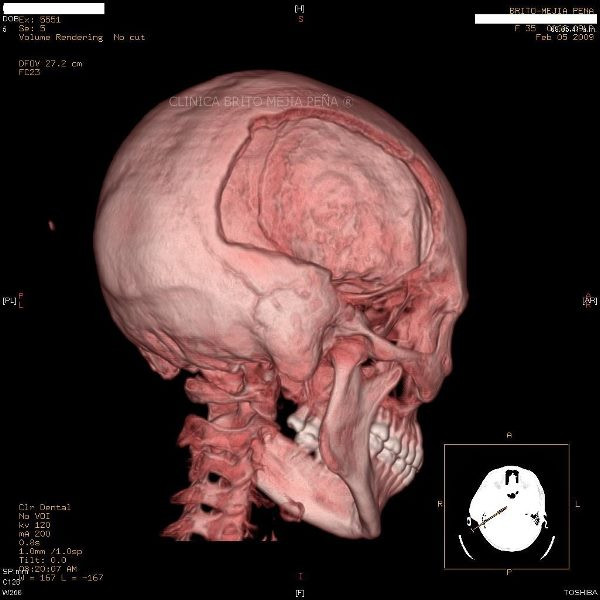

Envíado por BMP Imágenes Diagnósticas

BMP Imágenes Diagnósticas